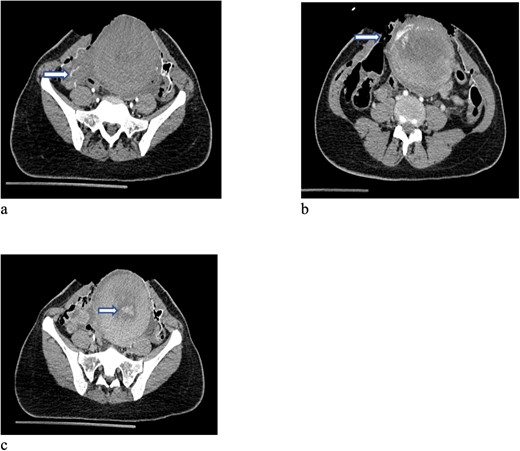

In total, 11 units of RBC, 12 units of fresh frozen plasma and 12 units of platelet concentrate, 6 units cryoprecipitate, Prothrombin complex concentrate (1000 units), fibrinogen (12 gram) and tranexamic acid were transfused (ROTEM-guided). The patient also received oxytocin (40 units) and methergine (0.4 mg) injections for the prevention and control of postpartum hemorrhage and then transferred to the hybrid operating room for imaging. Computed tomography (CT) scan revealed small laceration in the right lobe of the liver (segment 8) and another laceration at the upper pole of the right kidney without active bleeding. However, there was a focus of contrast blush seen in the arterial phase at the right lateral side of the uterine wall, which increased in the venous and delayed phases suggesting active arterial bleeding (Fig. 1a–c). The contrast extravasation is also seen within the endometrial cavity (Fig. 1c). Interventional radiologist was consulted, and he advised for close observation because these findings could be related to immediate postpartum uterine changes. The patient was transferred to the Trauma Intensive Care Unit (TICU) under mechanical ventilation, where she was hemodynamically stable. The last Intra-operative lab work showed hemoglobin level of 10 g and base excess was improved from −16 to −9 mEq/l. For completion of secondary survey, right shoulder X-ray was done and revealed a fracture of the right humerus head (Fig. 2). Few hours after admission to the TICU, the patient had post partum hemorrhage as frequent changing of blood-soaked packs was required and the hemoglobin dropped from 10 to 7 g. Sweeping of the uterine cavity was done by the obstetrician and small pieces of membranes was removed and no placental tissue was felt. Oxytocin drip 20 units in 500 ml was given intravenously and misoprostol 600 mcg was given rectally.

CT scan of the pelvis (a-c) after cesarean section revealed focus of contrast blush seen in the arterial phase at the right lateral side of the uterine wall, which increased in the venous and delayed phases suggesting active arterial bleeding. The contrast extravasation is also seen within the endometrial cavity.